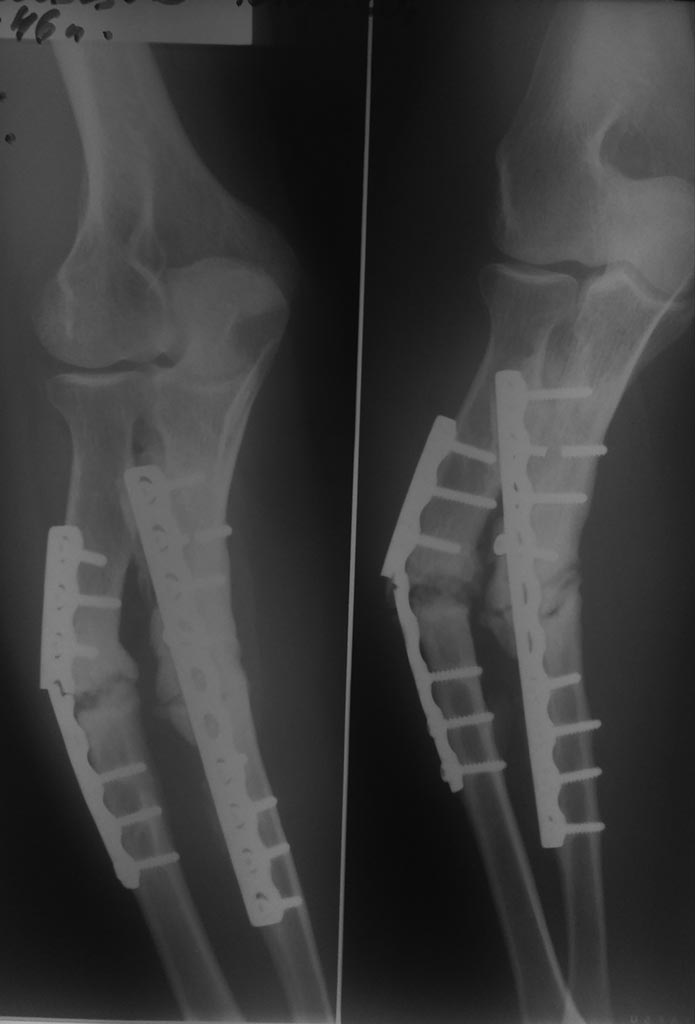

[Ortho] Ложный сустав обеих костей предплечья, несостоятельность остеосинтеза

Снимок

Андрей

Имя     : P_20200310_131019_1.jpg